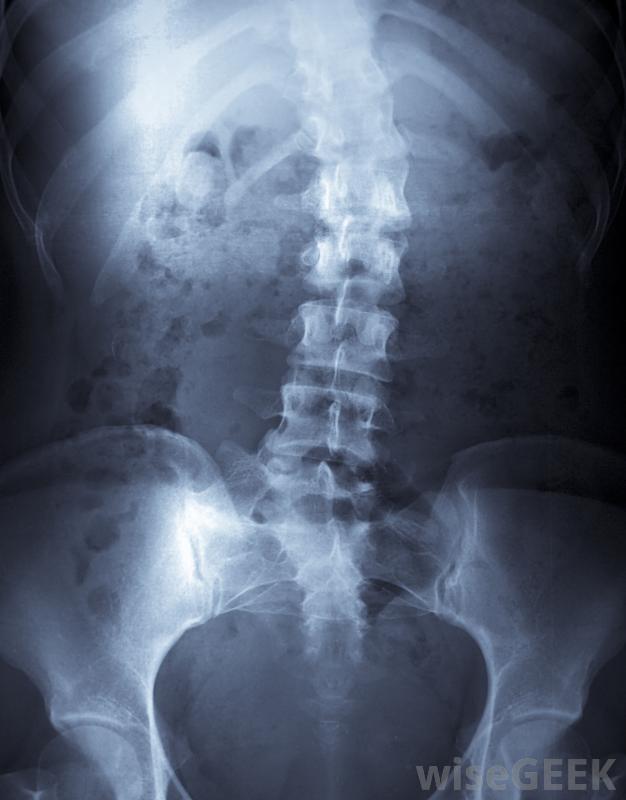

颈部和脊椎的X光片有许多脊椎疾病可以通过手术治疗,其中一些疾病,如脊柱侧凸或脊柱弯曲,可以自发发生;另一些,如脊椎脱臼,可由运动损伤或关节炎等退行性疾病引起。由于手术费用昂贵,需要长时间痛苦的恢复期,脊柱外科医生必须始终确保患者的疾病不能通过微创途径治疗。因此,他的工作很大一部分都致力于咨询病人,有时应非骨科医生的要求,以确定是否需要手术,他可以命令和检查x光片,并向病人解释手术过程,概述其风险和益处;如果患者决定手术,他可能还会解释如何准备以及康复期间的预期严重脊柱侧凸的患者可以进行脊柱手术。脊柱外科医生根据每个患者的情况进行不同的手术。有些是高度侵入性的。治疗例如,脊髓型颈椎病(CSM)是指从脊髓中取出骨头或椎间盘,以减轻对脊髓的压迫。脊椎融合术是将一段椎骨固定在一起以防止其移动,也是一种主要的治疗方法,用于治疗严重的脊柱侧凸和脊柱不稳等疾病,这种手术包括将金属棒或移植骨固定在脊柱的受影响区域,使该部分不能移动。